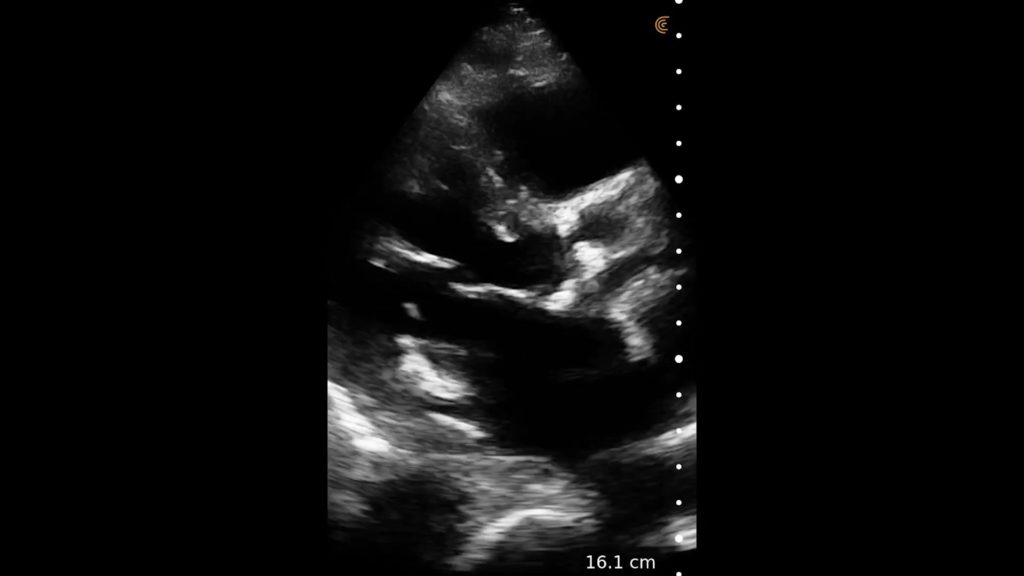

Cholecystitis

A dilated gallbladder with a gallstone in the neck, combined with wall thickening and pericholecystic fluid suggests cholecystitis, especially once combined with a Sonographic Murphy’s and liver enzymes.